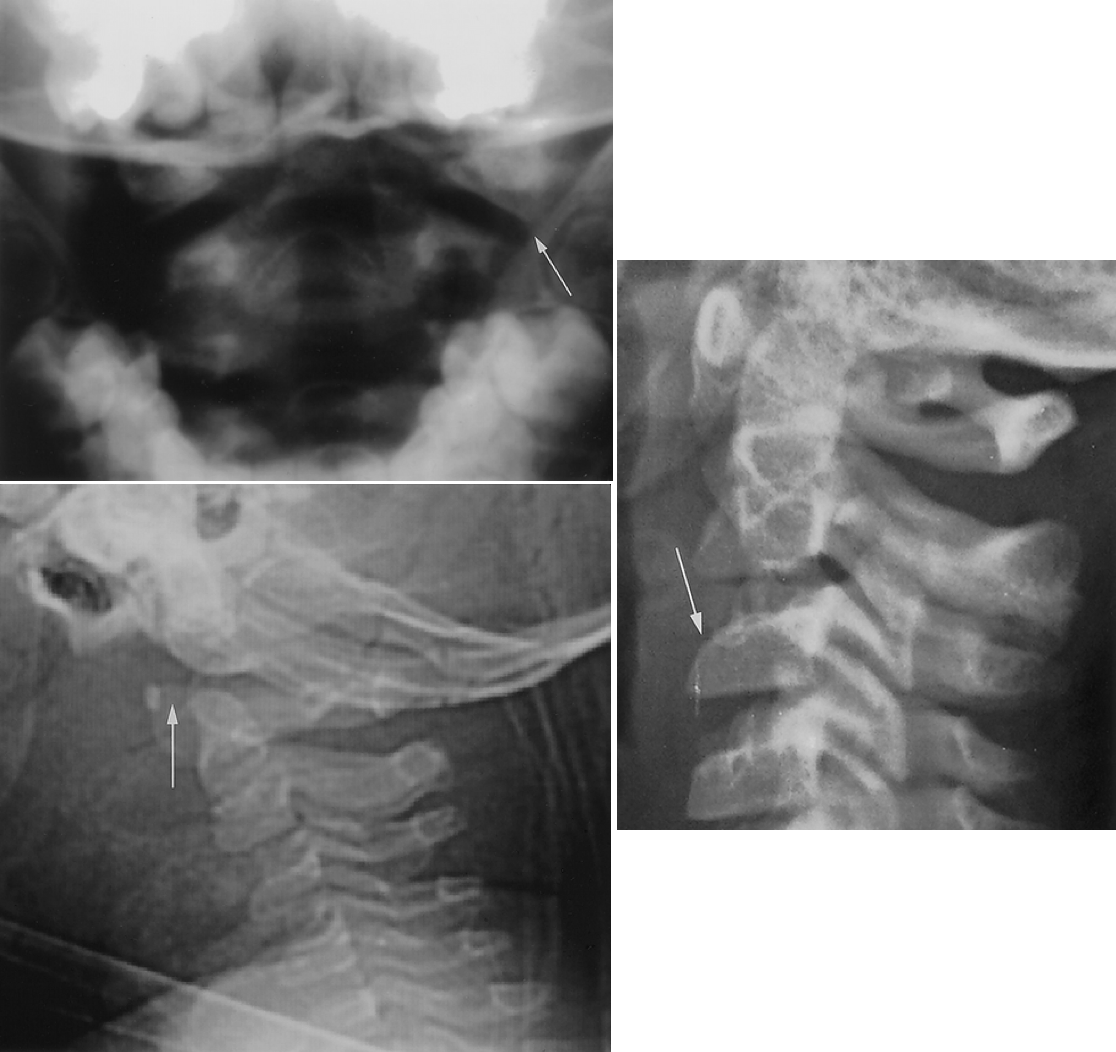

Jefferson Fracture

• Due to axial loading - force transmitted from occipital condyles to lateral masses of C1

• Burst fracture of C1. Usually fracture through anterior and posterior rings of C1

• Spreading of C1 lateral bodies on C2

• Asymmetry between odontoid process and lateral masses

• Stable if transverse ligament intact

• If distance between odontoid process and lateral mass > 6 mm, suspect transverse ligament injury

Atlantoaxial Rotary Subluxation

• Anterior facet of C1 becomes locked on facet of C2, impairing rotation at this joint

• May or may not be associated with C1-C2 dislocation

• May be caused by:

• Congenital syndromes (T21, NF1, Marfans, OI)

• Acquired (trauma, RPA - Grisel syndrome, URTI)

• Arthritides (RA, psoriatic, SLE, AS)

• In dislocation see widened ADI (should be less than 5 mm in children)

• In subluxation, normal ADI

• Loss of definition of craniocervical junction

• On AP one lateral mass appears wider and closer to midline

• On lateral anterior arch of C1 is not truly lateral

• Type 1: no displacement

• Type 2: 3 to 5 mm anterior displacement, atlas rotated on one lateral articular surface

• Type 3: greater than 5 mm anterior displacement, atlas rotated on both lateral articular surfaces

• Type 5: posterior displacement

• Hangman fracture or traumatic spondylolisthesis of the axis

• Hyperextension injury

• Virtually never seen in suicidal hanging (usually asphyxial)

• Most commonly seen in major trauma e.g. MCV

• Associated with fracture through bilateral pars interarticularis

• Anterior subluxation of C2 on C3 may be seen (don’t confuse with pseudosubluxation of C2 on C3) - look at posterior cervical line

• Posterior cervical line (line between anterior aspects of spinous processes of C1, 2, and 3) - should line up within 1 mm

• If the posterior cervical line does not overlap anterior aspect of spinous process of C2 by more than 2 mm, true injury is present

• Abnormal posterior cervical line suspect occult hangman fracture of C2